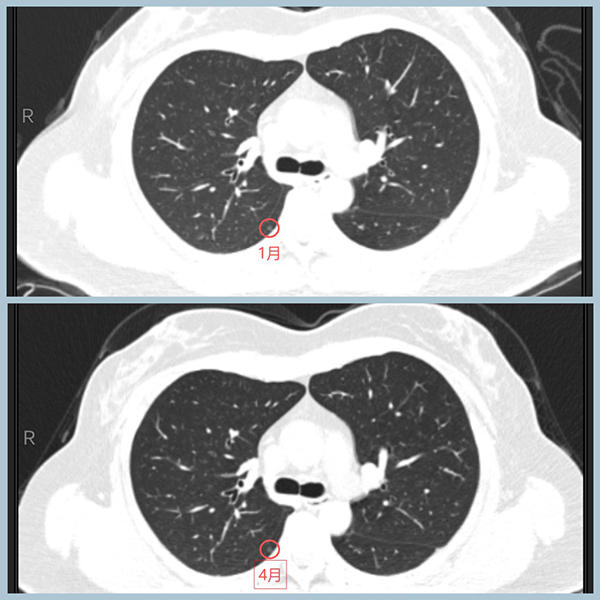

1、右肺两处结节,较大的在右中叶,恶性征象比较明显,3个月内有肉眼可见的变化:更加饱满,距胸膜更近。较小的在右下叶背段,约3mm,为纯磨玻璃结节,无明显变化,不典型增生可能大,可一并手术切除。